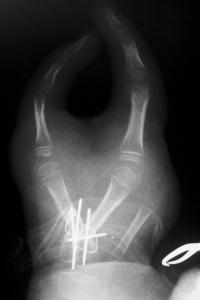

Palmar view: the working central and radial fingers lie adjacent in the same plane; pinch is impossible.

Closeup of fixation: crossed K wires augmented with interosseous wires. The stretched bifurcation of the common digital artery to the adjacent sides of the digits can be seen at the distal upper end of the image behind the retractor.